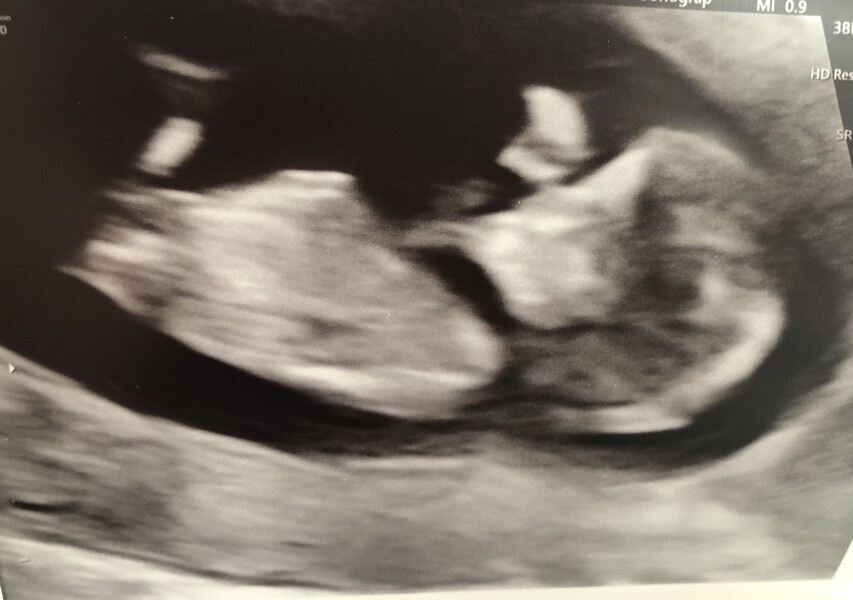

This was my scan at 11+2 with everything looking good so try not to worry about no symptoms.

Also does anyone think the skull looks girlish or boyish? I'm convinced I'm having a boy but DP thinks girl 😂 I'm starting to think it's a girly skull rounded skull 🤔